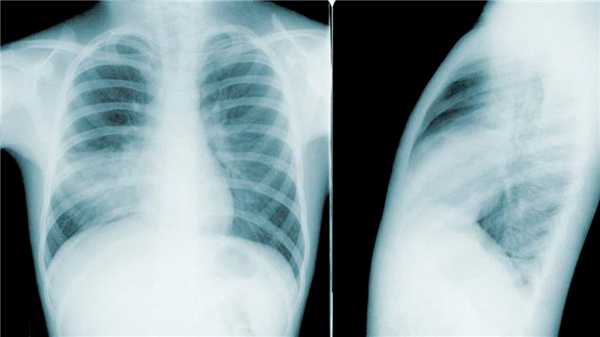

Рисунок 2: Двусторонняя пневмония на рентгеновском снимке в двух проекциях. Источник: PHIL CDC

- Рентгенография легких - позволяет выявить очаг воспаления.

- Компьютерная томография - назначается в случаях, когда рентгенография не показывает поражения легких, однако клиническая картина указывает на обратное. Компьютерная томография позволяет определить поражения легких по типу «матового стекла». Это изменения в легочной ткани на уровне альвеол. Такой характер воспаления часто отмечают при вирусных пневмониях, например, при гриппе или коронавирусной инфекции.